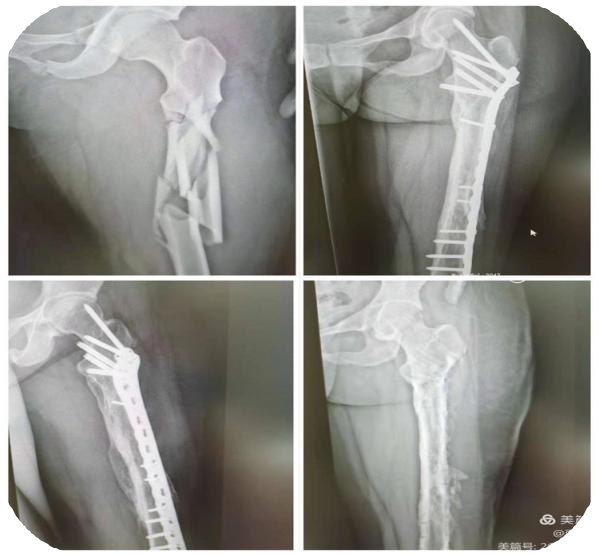

玉林市中西医结合骨科医院创伤二科特长创伤骨折脱位的中西结合治疗,普通手术或微创手术,包括各种关节置换治疗、腰椎疾患、骨质疏松症治疗等。熟练应用快速复位骨折牵引床、G臂、C臂及人工智能机器协助手术。科室有多种物理治疗仪,开展中医中药艾灸治疗等。对指导患者术后快速康复有丰富的临床经验。现有医护人员21名,副高主任医师有1名,主治医生6名。护理人员14名,其中主管护士有3名、护师有2名、护士有9名。